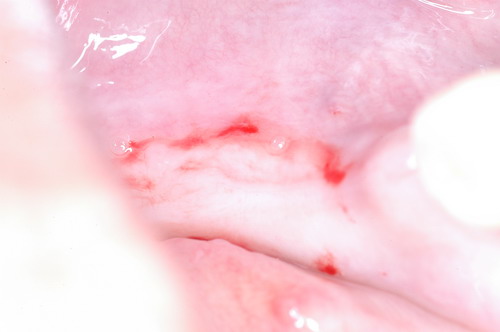

EL USO DEL ARCO GÓTICO DE GYSI , MEDIANTE UNA BÓVEDA PALATINA Y UN APOYO CENTRAL ÚNICO (BO PA YA CU) , EN LA UBICACIÓN DE LA RELACIÓN CÉNTRICA EN UN CASO DE GRAN LAXITUD TENDINOSA CAPSULAR. EL PACIENTE SE PRESENTA A CONSULTA CON UNA EDENTACIÓN PARCIAL, Y GRADO DE MOVILIDAD EXTREMO EN TODAS SUS PIEZAS REMANENTES. SE ESTUDIA EL CASO RADIOGRÁFICA Y CLÍNICAMENTE , Y EL PACIENTE RELATA ESTAR EN ESE ESTADO DESDE HACE MUCHO AÑOS. AL MANIPULAR LA MANDÍBULA EN UN INTENTO DE CONOCER EL ESTADO MUSCULAR DEL SISTEMA, SE OBSERVA UNA GRAN LABILIDAD TENDINOSA CAPSULAR QUE SE MANIFIESTA EN UNA HIPER LAXITUD EN LOS MOVIMIENTOS MANUALMENTE INDUCIDOS DE AMBOS CÓNDILOS DENTRO DE LA CAVIDAD. SE TOMAN IMPRESIONES Y SE MONTA EN UN ARTICULADOR SEMI AJUSTABLE , CORTANDO EN EL YESO LAS PIEZAS QUE SERÁN EXTIRPADAS , CONSERVANDO UNICAMENTE , AMBOS PRIMEROS PREMOLARES INFERIORES , QUE SERÁN UTILIZADOS PARA RETENER MEDIANTE RETENEDORES ELÁSTICOS LA PRÓTESIS INFERIOR , EN LA PRESUNCIÓN DE LA HIPERMOVILIDAD A QUE SERÁ SOMETIDA DADO QUE EN LA GRAN REABSORCIÓN ÓSEA , ES FRECUENTE EL ACERCAMIENTO DE TODAS LAS INSERCIONES MUSCULARES A LA PORCIÓN SUPERIOR DEL REBORDE ÓSEO , LO QUE ATENTARÁ CONTRA LA ESTABILIDAD DE DICHA PRÓTESIS PROVISIONAL. EN UNA PRIMERA SESIÓN CLÍNICO QUIRÚRGICA , SE EXODONCIA TODO EL SECTOR INCISIVO Y CANINO INFERIOR , Y AL OBSERVAR EL REMANENTE ÓSEO CANINO DE AMBOS LADOS , SE IMPLANTA EN FORMA INMEDIATA . TANSCURRIDOS DOS MESES , DONDE LA CICATRIZACIÓN ES ADECUADA , Y LA DINÁMICA MANDIBULAR ACEPTABLE , SE PROCEDE A LA ETAPA QUIRÚRGICA IMPLANTARIA MEDIANTE IMPLANTES SEMI SUMERGIDOS, CON ALGUNAS ZONAS DE REGENERCIÓN ÓSEA GUIADA FIG17 FIG18 FIG19 FIG26 DURANTE LA ETAPA DE CICATRIZACIÓN DE ESTE NUEVO ABORDAJE QUIRÚRGICO , SE ENDODONCIAN AMBOS PREMOLARES INFERIORES CONSERVADOS , LOS QUE EN UN FUTURO , CUANDO YA NO SIRVAN PARA RETENER LA PRÓTESIS REMOVIBLE PROVISORIA INFERIOR , SERÁN CORTADOS COMO RESERVA DE CAPITAL ÓSEO O BIEN COMO ELEMENTO RETENEDOR ANTE CUALQUIER TIPO DE INCIDENCIA IMPLANTARIA. ABORDAMOS LA ETAPA PRIMARIA PROTÉTICA , UNA VEZ TRANSCURRIDOS TRES MESES, MEDIANTE LA UTILIZACIÓN DE CUBETAS INDIVIDUALES , A LAS QUE REALIZAMOS UN RECORTE MUSCULAR EN BASE A STENS VERDE , COMO SI DE UNA PRÓTESIS COMPLETA SE TRATARA. DE ESE MONTAJE OBTENEMOS DOS RODETES DE METACRILATO , PERFECTAMENTE ADAPTADOS A LOS MODELOS FUNCIONALES , A LOS QUE LES OTORGAMOS LA PLANIMETRÍA DERIVADA DEL PARALELISMO CON EL PLANO DE FRANKFURT , Y UNA ALTURA (DV) QUE RESULTA DE LOS MÉTODOS MÉTRICOS DE DIMENSIÓN VERTICAL… Y QUE NOS SERVIRAN ADEMÁS DE TOMAR UNA NUEVA IMPRESIÓN FUNCIONAL MEDIANTE RECORTE MUSCULAR , PARA ADAPTAR UN DISPOSITIVO CONSISENTE EN UNA BÓVEDA PALATINA SUPERIOR , Y UN TORNILLO CENTRAL INFERIOR , LOS QUE DESPUÉS DE UN ENTRENAMIENTO ADECUADO DEL ENFERMO , NOS PERMITIRÁ REPRODUCIR EN EL BÓVEDA , EL ARCO GÓTICO DE GYSI , ENCONTRANDO DE ESTA MANERA LA OCLUSIÓN EN RELACIÓN CÉNTRICA. ACTUALMENTE ESTE MÉTODO HA SIDO RECREADO MEDIANTE LA DENOMINACIÓN DE: FIG50 FIG51 FIG52 OBTENIDO EL DIBUJO DEL ARCO GÓTICO , INSINUAMOS EN EL VÉRTICE DEL MISMO UNA PERFORACIÓN QUE FIJARÁ LA PUNTA DEL TORNILLO EN ESA POSICIÓN: RELACIÓN CÉNTICA FIG55 FIG56 FIG57 CON ESTOS PARÁMETROS SE CONSTRUYEN DOS SOBREDENTADURAS ABROCHADAS EN RÓTULAS SUPRA IMPLANTES , QUE LE OTORGAN FIJACIÓN SUFICIENTE , DANDO A LA OCLUSIÓN TODOS LOS ELEMENTOS DE UNA: OCLUSIÓN MUTUAMENTE COMPARTIDA, REFERENCIA II CON UN ESQUEMA OCLUSAL DE : FUNCIÓN DE GRUPO BILATERAL POSTERIOR DE ACCIÓN CANINA DESPUÉS DE LAS REVISIONES PERTINENTES A LA SEMANA , EL MES Y LOS SEIS MESES DE TERMINADA LA REHABILITACIÓN , SE CITA AL ENFERMO PARA UN NUEVO CONTROL AL AÑO Y MEDIO Y SE OBSERVA UNA PERFECTA SITUACIÓN TISULAR , CLINICA Y RADIOGRAFICAMENTE CONTROLADA , Y ADEMÁS LA PERMANENCIA DEL MISMO ESQUEMA OCLUSAL OTORGADO DESDE EL PRINCIPIO. SE CONTROLA RADIOGRAFICAMENTE Y SE DA EL ALTA DEFINITIVA RECOMENDANDO EL CONTROL DOS VECES AL AÑO. REFERENCIAS: I : II. : III: